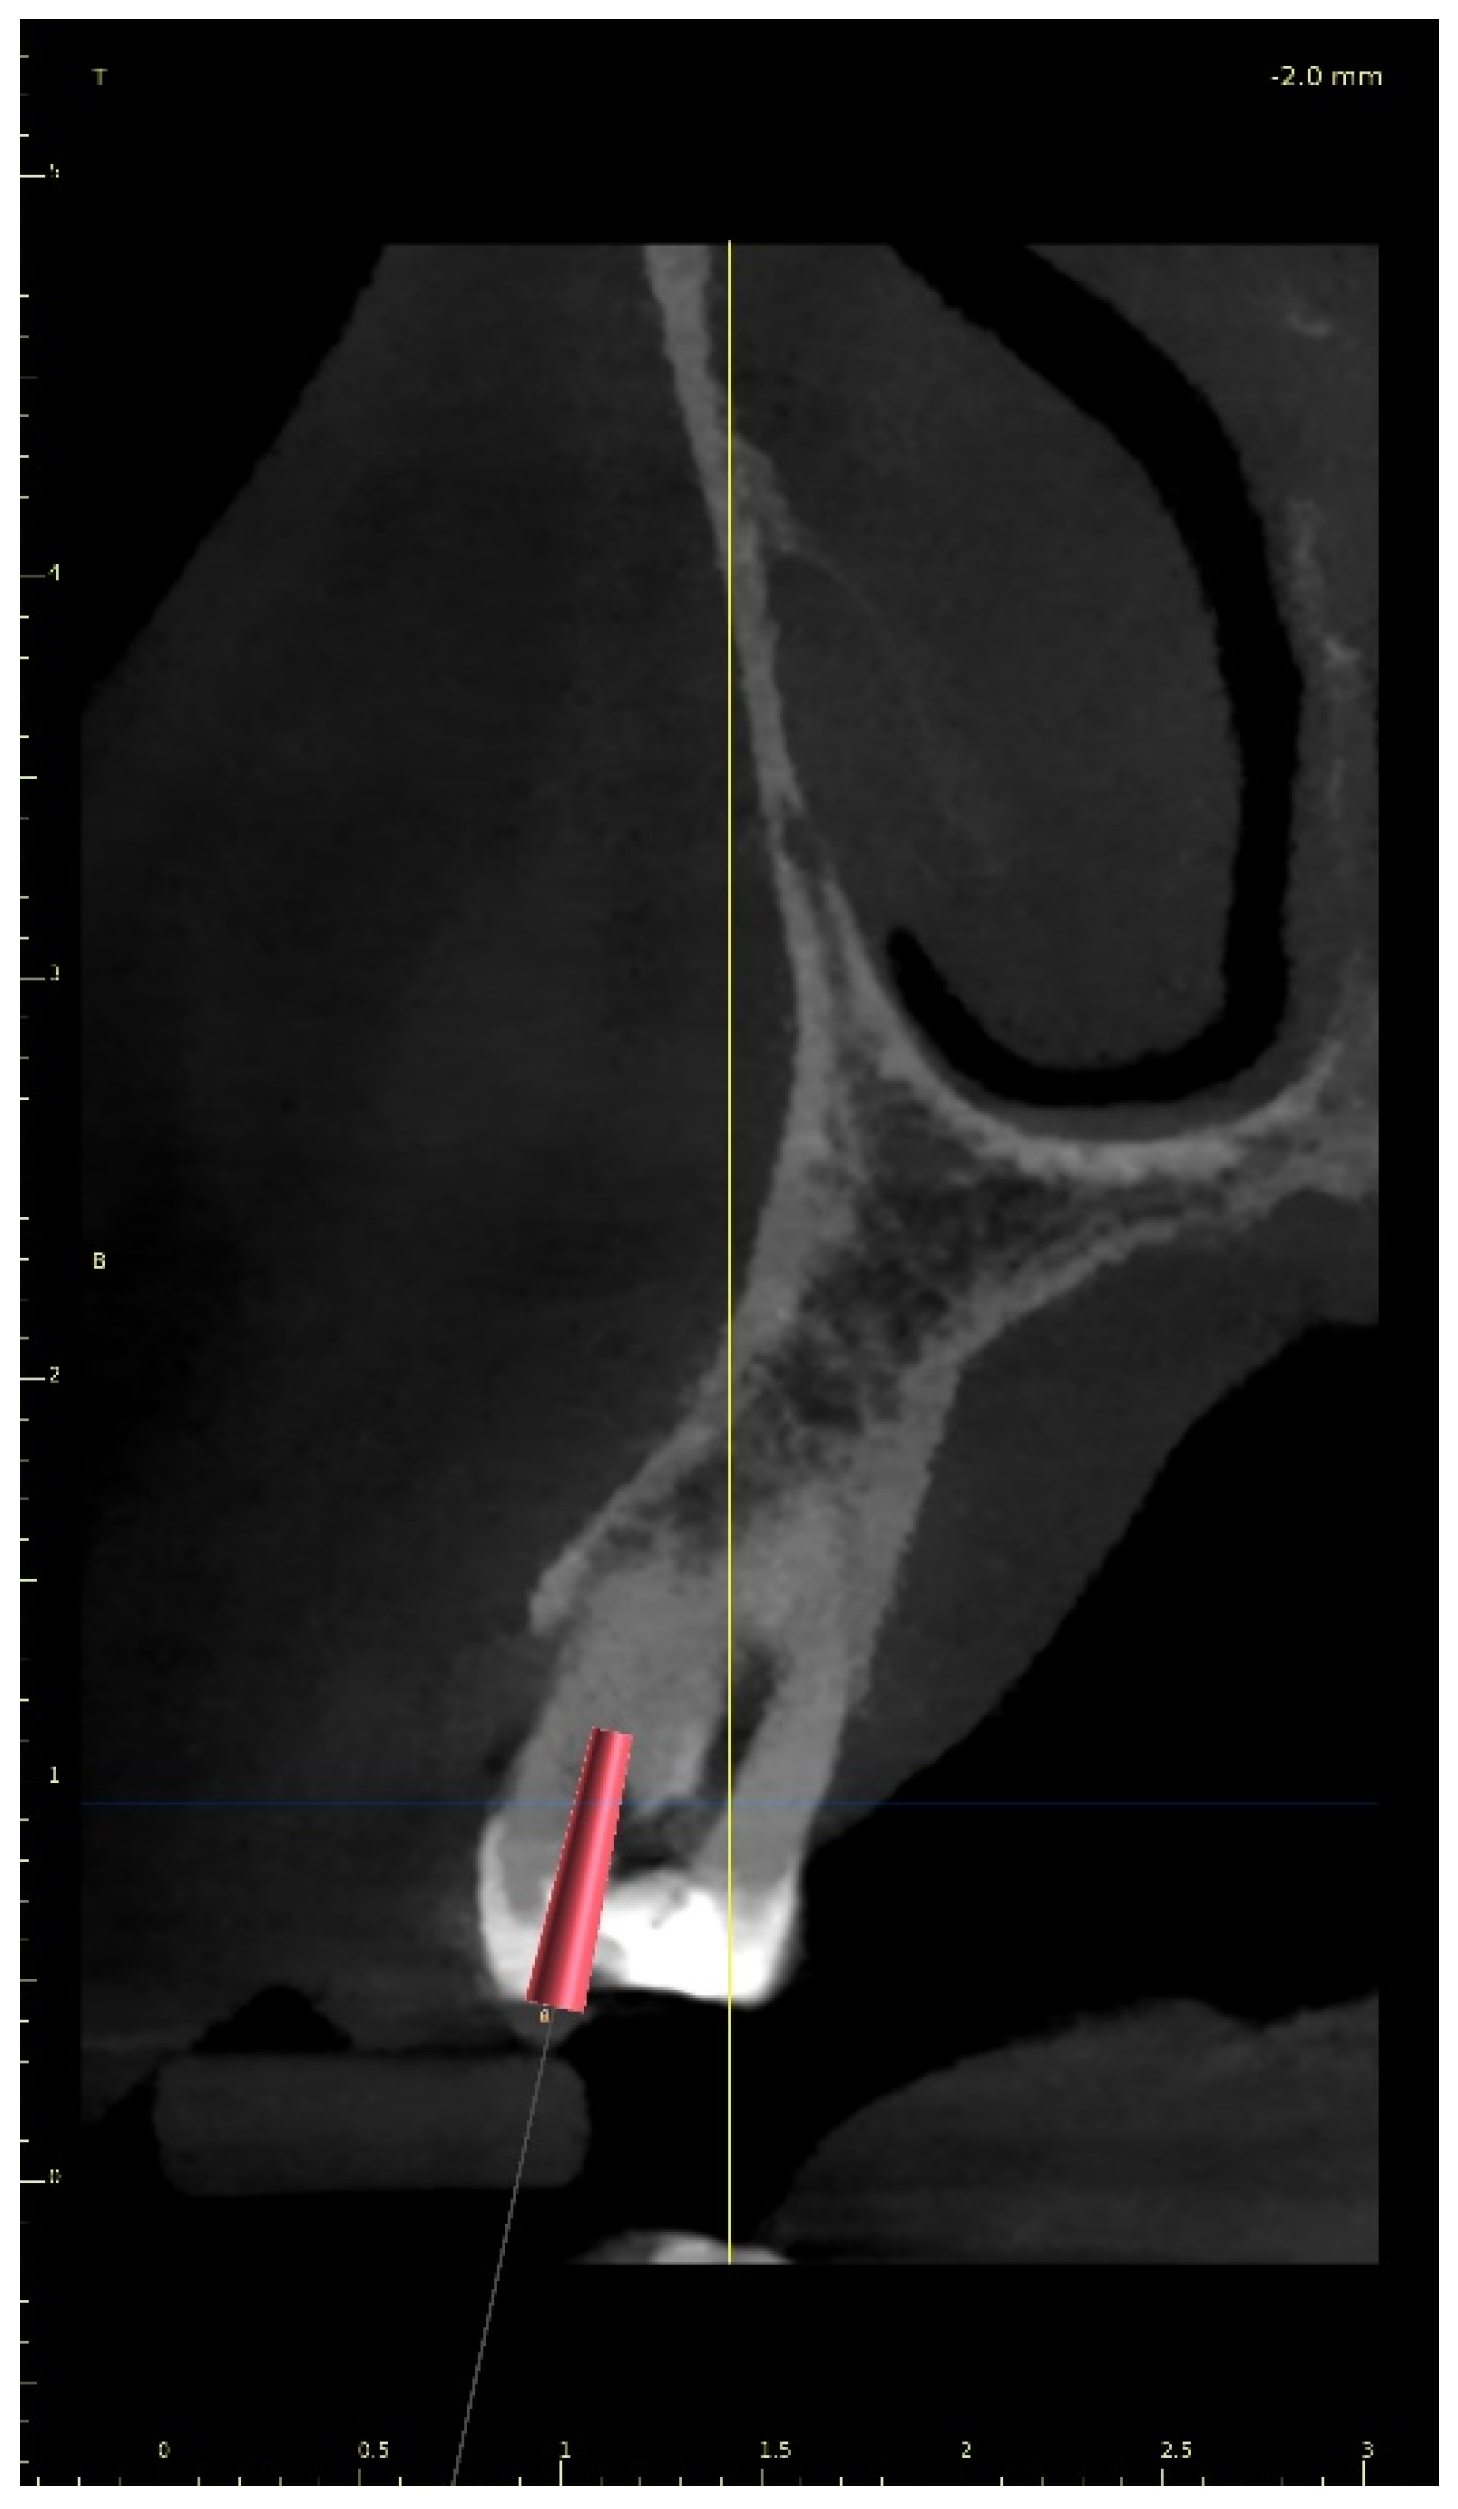

After the implant position was accepted by a clinician, an endodontic guide (teeth-supported) was designed for a sleeveless, static navigation of the image obtained from an intraoral scan (Figure 12). The guide covered the labial and palatal surfaces of the adjacent teeth (13-23) to obtain adequate intraoral stabilization. The use of stabilizing pins is unnecessary in such cases. The guide tube was designed so that the top of the sleeve was 21 mm from the radiographically visible root canal lumen. The guide sleeve was 6 mm long and 1.5 mm in diameter. The endodontic guide was printed on a resin 3D printer (Phrozen Sonic Mini 4K) using a transparent resin designed for printing surgical guides (NextDent SG)—a class IIa product that can be used in the oral cavity (Figure 13). Post-processing was conducted in accordance with the resin manufacturer’s instructions to avoid dimensional changes [24]. A master model was printed to check the accuracy of the guide’s fitting (Figure 14).

As in the previous case, the virtual drill orientation was established in the centre of the root. The top of the sleeve was 14 mm from the bottom of the tooth chamber. The guide sleeve was 6 mm long and 1 mm in diameter (Figure 26). The template with engraved canal markings was equipped with a window for assessing the correctness of the guide’s intraoral placement (Figure 27). The buccal canal was cautiously negotiated through the guide with a size 10 file (C-Pilot #10) instead of rotated burs. The root canal orifice was reached at a length of 15 mm from the top of the guide sleeve. The time needed to localize the canal path in this case was approximately 10 min. The file was taken to the working length and a conventional root canal treatment followed (Figure 28).